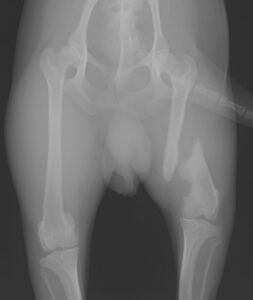

犬の門脈体循環シャント(PSS)血管結紮術 2022/11/22 外科 詳細はこちら 先天性眼瞼内反症 2022/05/17 外科 詳細はこちら 角膜潰瘍_結膜皮弁法 2021/12/27 外科 詳細はこちら [パテラ]膝蓋骨内方脱臼整復-脛骨粗面転移術 2021/12/25 外科 詳細はこちら [でべそ]犬の臍ヘルニア整復術 2017/05/23 外科 詳細はこちら 犬の肛門嚢摘出 2016/10/10 外科 詳細はこちら 内閉鎖筋転移と直腸固定による会陰ヘルニア整復術 2016/09/16 外科 詳細はこちら 猫の断脚 2016/07/23 外科 詳細はこちら 猫の趾端部軟部組織肉腫 2016/04/14 外科 詳細はこちら